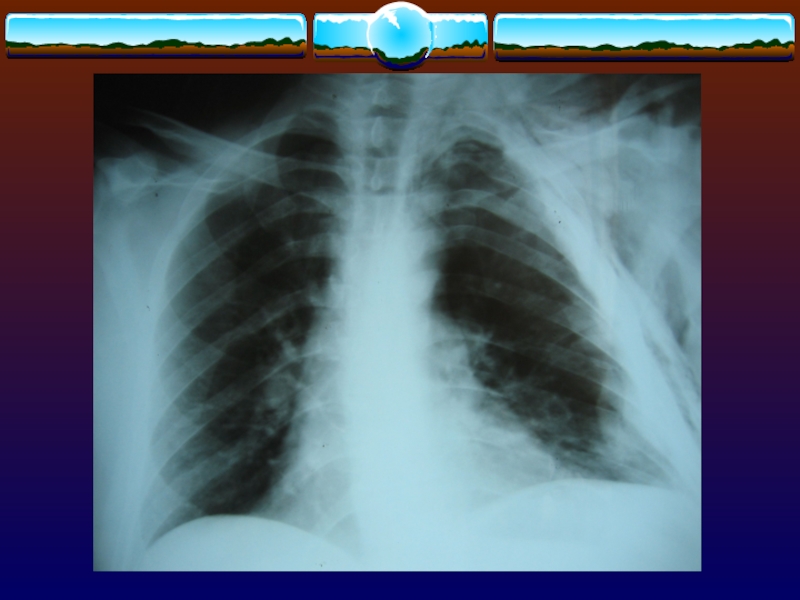

Слайд 14Ушиб легкого

Воздействие тупой травмирующей силы на грудную клетку приводит

к повреждению паренхимы легких, что сопровождается выходом крови и белка

в интерстициальные ткани.

Клинические проявления достигают пика через 48-72 ч

Ушиб легкого Воздействие тупой травмирующей силы на грудную клетку приводит к повреждению паренхимы легких, что сопровождается выходом

Слайд 15Клинические проявления

Нарастающая одышка, тахипноэ.

Уменьшается насыщение крови кислородом.

При рентгенографии - плотный

лёгочный инфильтрат над поврежденной областью, но определяется только через 12-24

ч после повреждения.

Степень прогрессирования клинических и рентгенологических данных соответствует тяжести поражения.

При КТ диагноз возможно подтвердить раньше, чем при обзорной рентгенография.

Клинические проявленияНарастающая одышка, тахипноэ.Уменьшается насыщение крови кислородом.При рентгенографии - плотный лёгочный инфильтрат над поврежденной областью, но определяется